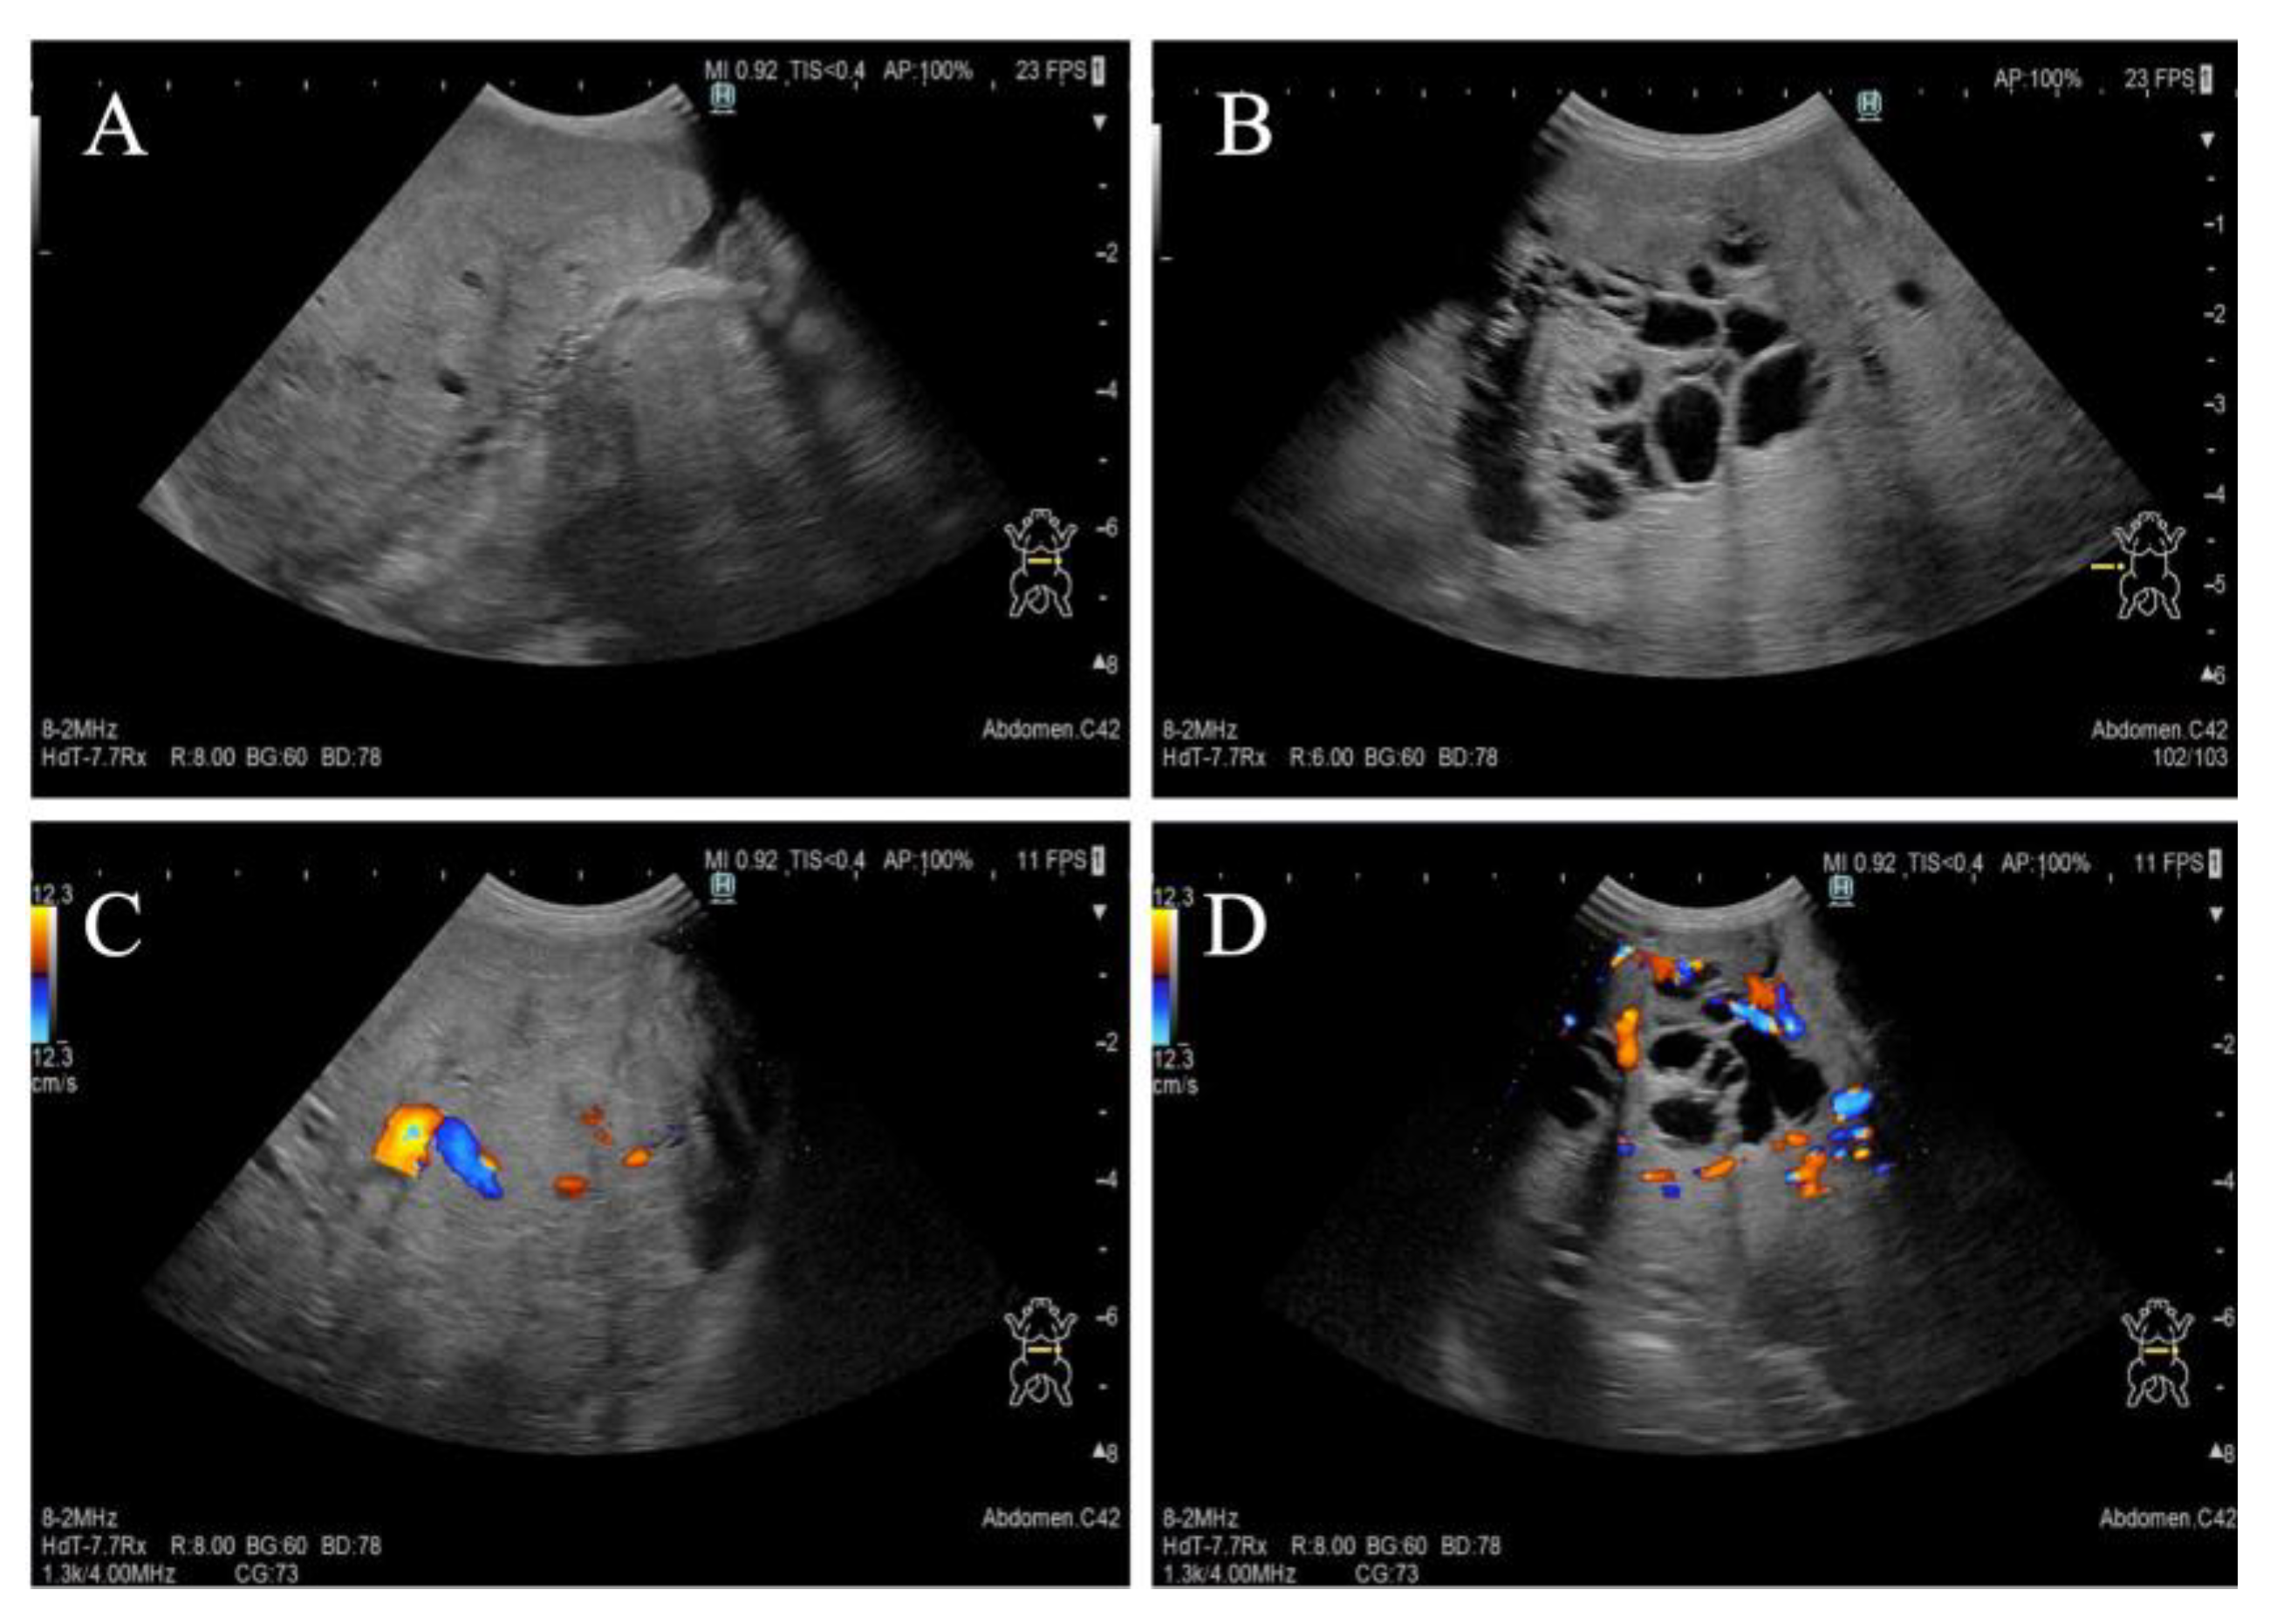

A one-year-and-two-month-old, intact female Pomeranian dog from a rescue organization was referred to the authors’ medical facility for the investigation of abdominal distension. The dog had been used for breeding and had a history of giving birth; however, specific details regarding the birth were unknown. According to the rescue organization, the dog had experienced one estrus before the operation. Clinically, at the time of presentation, the dog was in an anestrus stage. The dog had no history of abnormal estrous bleeding and had a normal estrous cycle. Upon the initial consultation, the patient showed no abnormality in its activity level, appetite, defecation, and urination, and there was no evidence of dyspnea due to abdominal distention. The dog weighed 3.9 kg with a body condition score of 3/5 and showed a severe abdominal distension but without any sign of pain or discomfort. Physical examination revealed a body temperature of 38.5 °C, with a heart rate of 144 beats per minute and a respiratory rate of 36 breaths per minute. The visible mucous membranes appeared pale pink, and no swelling or enlargement of the superficial lymph nodes was observed. Complete blood count (IDEXX ProCyte Dx; IDEXX Laboratories, Inc., Westbrook, ME, USA) revealed mild leukocytosis (22,800/μL; reference interval (RI) 2870–17,020/μL) and mild anemia (hematocrit: 30.0%; RI 30.3–52.3%). Serum biochemical analyses were performed using the (DRI-CHEM NX700; FUJIFILM Corporation, Tokyo, Japan), and the results (albumin; 2.7 g/dL, blood urea nitrogen; 11.7 mg/dL, alanine aminotransferase; 15 U/L, sodium; 139 mEq/L, potassium; 3.8 mEq/L, chlorine; 102 mEq/L) were within reference intervals. Thoracic radiography did not show any apparent abnormalities. Abdominal radiography revealed a left abdominal mass occupying the area from the last rib to the pelvis with displacement of the small intestine to the right, along with decreased contrast of intra-abdominal organs (Figure 1A,B). No other obvious abdominal abnormalities were noted. An abdominal ultrasound (ALOKA LISENDO880; Hitachi Ltd., Tokyo, Japan) detected a mass lesion extending throughout the left abdomen, with the mass located just ventral to the left kidney and in close contact. The left ovary and uterus were not identified around the left kidney. The mass exhibited heterogeneous echogenicity depending on the region, predominantly consisted of a homogeneous parenchymal area (Figure 2A), but partially contained a cystic area (Figure 2B). For the cystic area, anechoic regions were scattered within the cyst. Color Doppler examination revealed relatively poor vascularity in the parenchymal areas (Figure 2C) and abundant blood flow in the cystic areas (Figure 2D). A small amount of peritoneal effusion was observed around the bladder but was too small to collect for analysis. Echocardiography showed no obvious abnormalities in cardiac function. Based on these findings, a tentative diagnosis of an intra-abdominal mass near the left kidney suspected to originate from the female reproductive organ was made. Differential diagnoses included ovarian tumors (such as epithelial tumors, sex cord-stromal tumors, germ cell tumors, mesenchymal tumors) and uterine tumors (such as mesenchymal tumors, epithelial tumors).

Figure 2. Preoperative abdominal ultrasound imaging. (A) Homogenous parenchymal area of the mass. (B) Cystic area with anechoic region. (C) Color Doppler imaging of parenchymal areas revealing relatively poor vascularity. (D) Color Doppler imaging of cystic area revealing abundant blood flow.